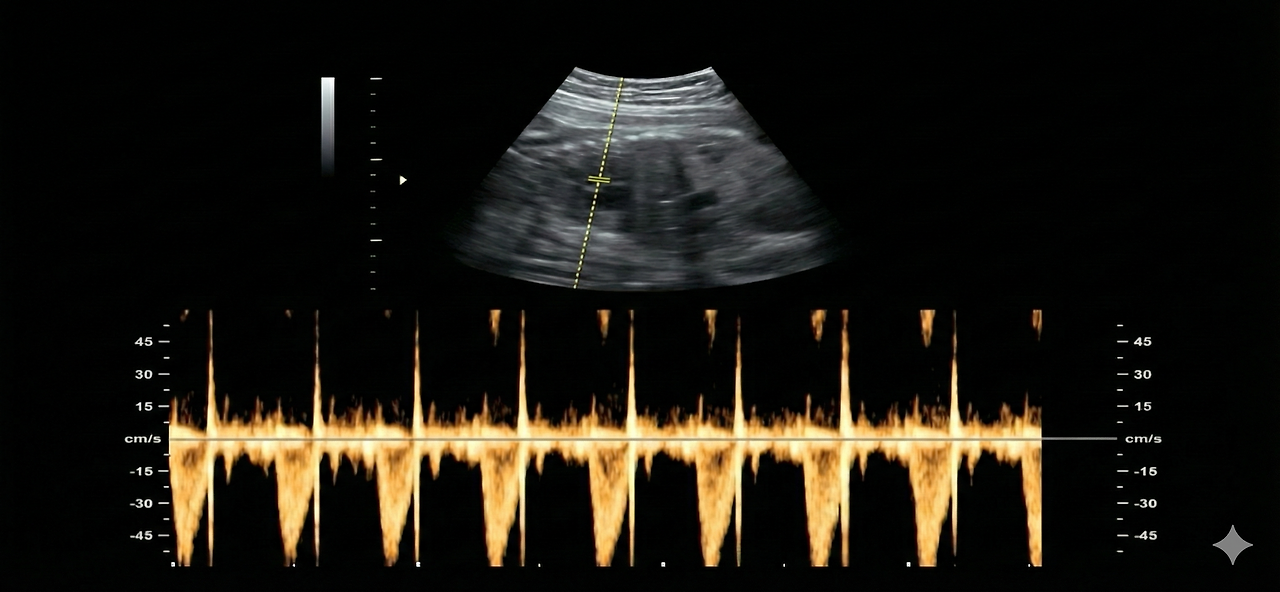

days-10_e.png < 콩닥콩닥 심장박동. 딸꾹질 보다 훨씬 빠르더라. >